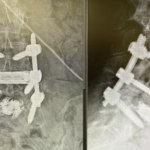

The dualX® LLIF solution is a comprehensive expandable interbody cage system for small portal access. dualX® LLIF is designed to minimize neural retraction while achieving maximum implant geometry.

The procedure is performed completely through an 18mm opening, reducing the potential psoas retraction up to 50%.

Vertical expansion assists in direct and indirect decompression

Heights 7mm* expanding to 17mm*

Width 13mm expanding to 22mm

Final Length 40 to 60mm

0°, 7°, 12° and 18° Lordosis*